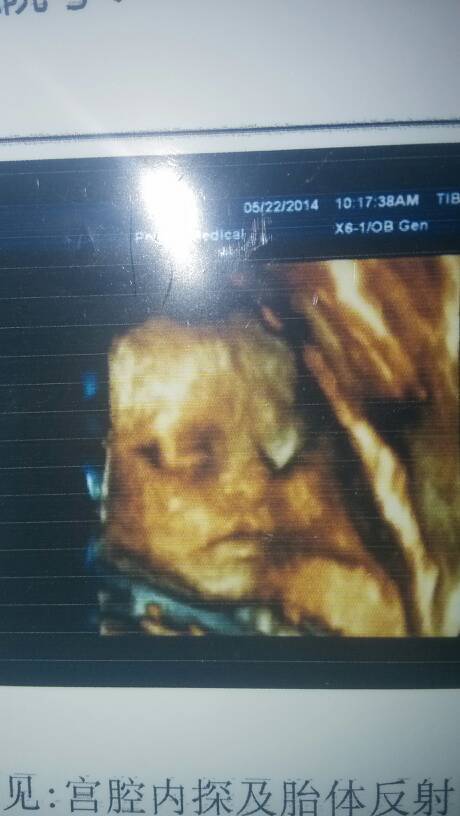

孕妇六个月,今天做四维去了?医生说大致没什么,回家一看彩超感觉胎儿的嘴不完整,是不是唇裂? 点击展开 匿名用户 2014-05-22 22:29 为您推荐: 其他回答 病情分析: 您好,根据你的情况,孩子做了思维彩超,你感觉最不完整。 指导意见: 不是这样的,孩子这个月份长的都是丑丑的,没有问题。大一些就好了。还没有发育好呢。 匿名用户 2014-05-23 10:11 相关问题 几个月做四维彩超能看出胎儿唇裂 今天做的四维彩超,医生说胎儿双肾集合系统轻度分离,很担心